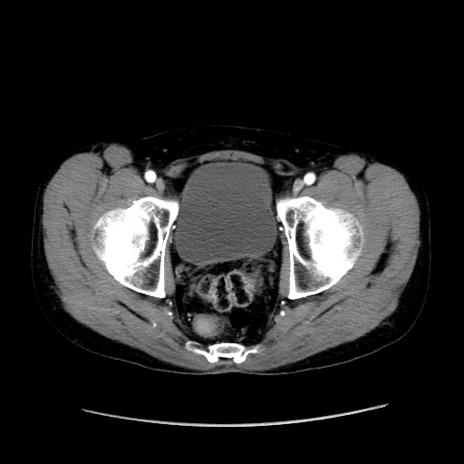

症例37(横断像)

【症例】40歳代 男性

【主訴】腹痛

【現病歴】4時間ほど前に電車に乗車中に臍部上より腹痛出現。徐々に増悪し起立困難となり、救急外来受診。生ものは数日食べていない。今朝お雑煮を食べた。

【身体所見】BT 36.8℃、BP 117/84mmHg、HR 91/min、SpO2 97%、苦悶様、腹部:臍上部広範囲圧痛あり、反跳痛±

【データ】WBC 8100、CRP 0.03